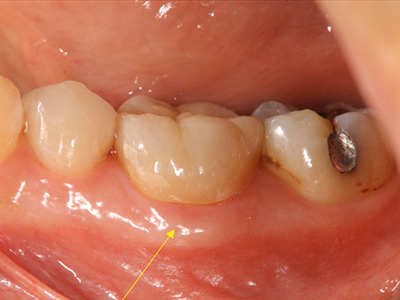

感染根管治療(リトリートメント)

右下奥歯で咬むと違和感がある/歯ぐきが腫れてきた

治療内容

- ① 顕微鏡視下根管治療(マイクロエンド)

- ② 根管拡大・洗浄2回

- ③ 2ヶ月経過観察で再生反応確認後に根管充填

- ④ マイクロスコープ下でファイバーコア築造+セラミック冠装着

約3ヶ月半(1回の治療:1~2時間)

- マイクロエンド132,000円

- ファイバーコア 22,000円

- 仮歯 6,600円

- セラミック冠 165,000円

- 術後の腫れ・痛み・出血

- 慢性根尖性歯周炎が再発する可能性

- 定期的なチェックが必要

サイナストラクトは消失し、CTでも透過像の改善を確認。

術後数日で痛み消失し、セラミック装着後も良好な咀嚼が可能。

現在は年1 回の定期チェックを継続中。